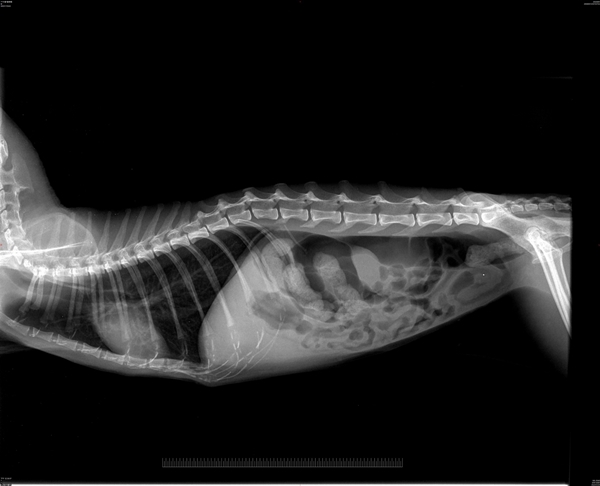

抓起來送到醫院動物近況說明: 貓咪一到醫院, 發現體溫過低有嚴重的脫水.

口腔檢查發現有嚴重口炎, 還有一個腫瘤腫塊.

預計在敗血症穩定後手術切除.

在血檢發現有黃膽脂肪肝的現象, 有流鼻涕上呼吸道感染. 因為有敗血症給予三代抗生素治療.